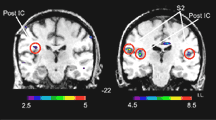

Chez les sujets d’un groupe témoin soumis à la même expérience, l’imagerie cérébrale a révélé deux zones d’activation neuronale étroitement liées, le cortex insulaire et l’aire somatosensorielle (voir l’illustration). Ces sujets étaient en mesure de décrire à la fois les caractéristiques objectives du toucher (vitesse, direction, force) et ses caractéristiques émotives associées au plaisir et à la sensualité. Chez la patiente montréalaise, seul le cortex insulaire était activé et elle ne pouvait que ressentir la valeur émotionnelle du toucher.

À droite, l’imagerie cérébrale montre l’activation de l’aire somatosensorielle (S2) et du cortex insulaire (Post IC) chez un sujet normal en réponse à une caresse. À gauche, la même caresse n’active que le cortex insulaire — zone associée au plaisir du toucher — chez la patiente privée de sensations tactiles. |

«Ces deux zones sont donc responsables de fonctions différentes dans l’analyse du toucher», en conclut Yves Lamarre. L’aire somatosensorielle décode les aspects objectifs du geste et le cortex insulaire nous en fait éprouver l’intention ou la charge émotive. Le cortex insulaire est d’ailleurs activé lorsque des sujets sont soumis à des stimulus visuels évoquant l’amour romantique ou l’excitation sexuelle. Selon le chercheur, ceci montre l’importance du rôle des caresses et de la communication tactile dans les rapports amoureux.